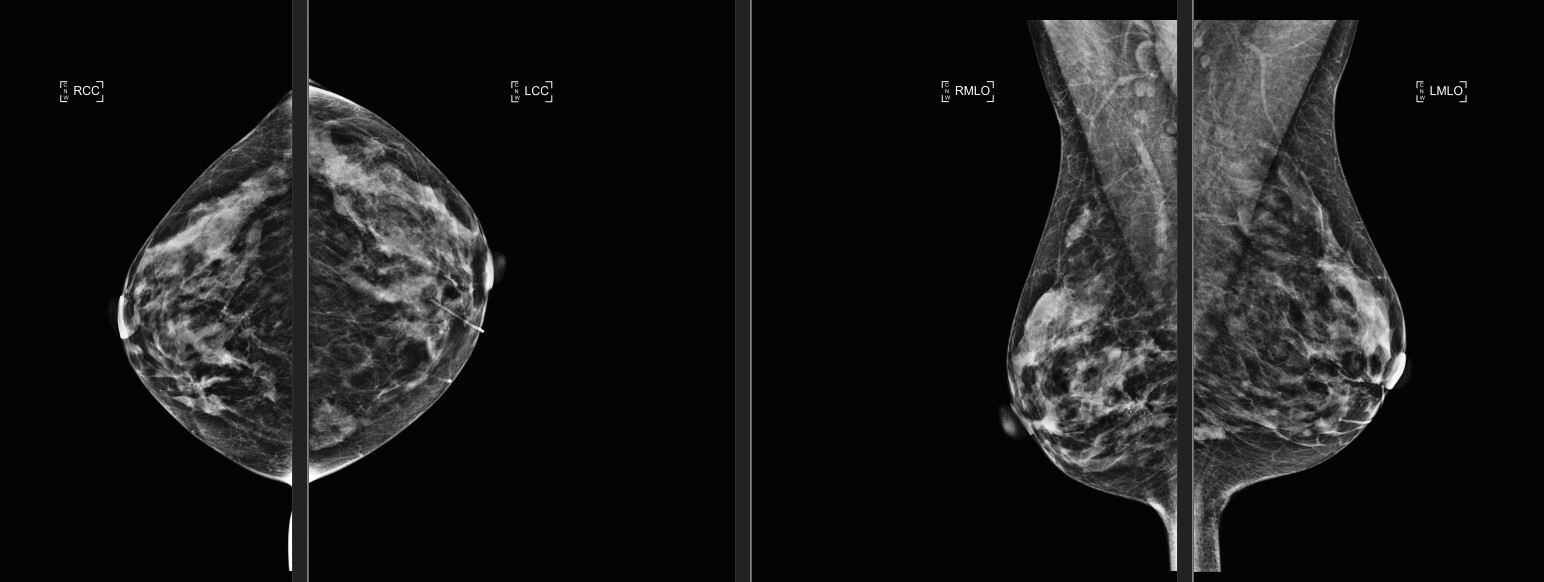

One imaging manager at a leading breast center told us that her radiologists were so impressed during their trial evaluation that using Bella Blankets allowed them to see more chest wall tissue in the CC views and also saw improved visualization in the MLO views, that they now use them for all their patients.